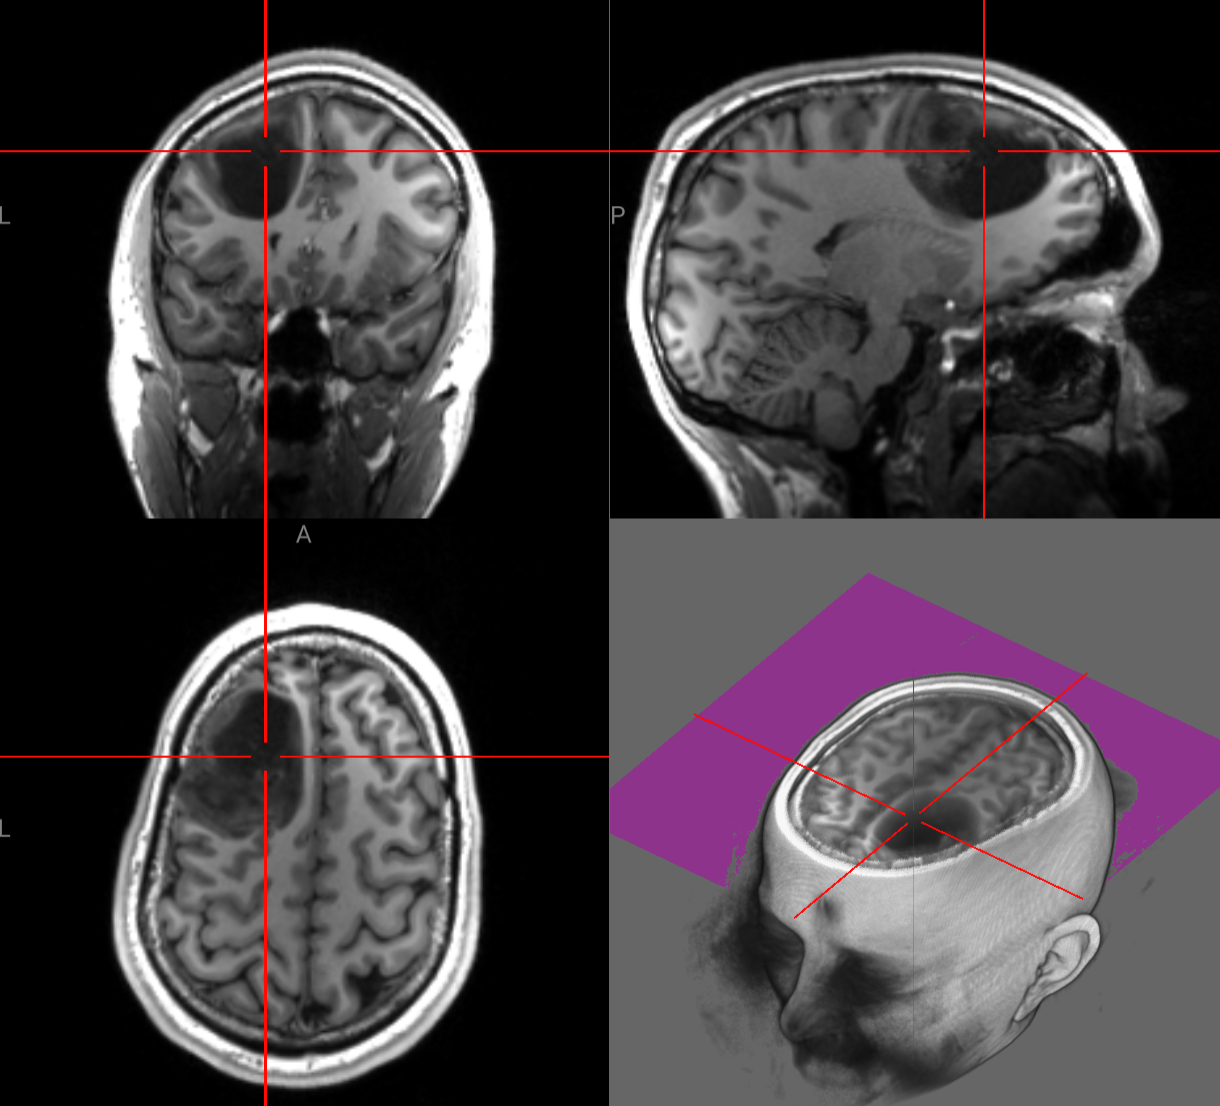

As you may or may not be aware (surprise!) Spencer found out on Friday, February 13th that he has a brain tumor in his left frontal lobe. He’s named it Philip, is in good spirits, has a fantastic support system, and is geeking out over all of the medical imaging he’s had done and will continue to receive at NYU Langone.